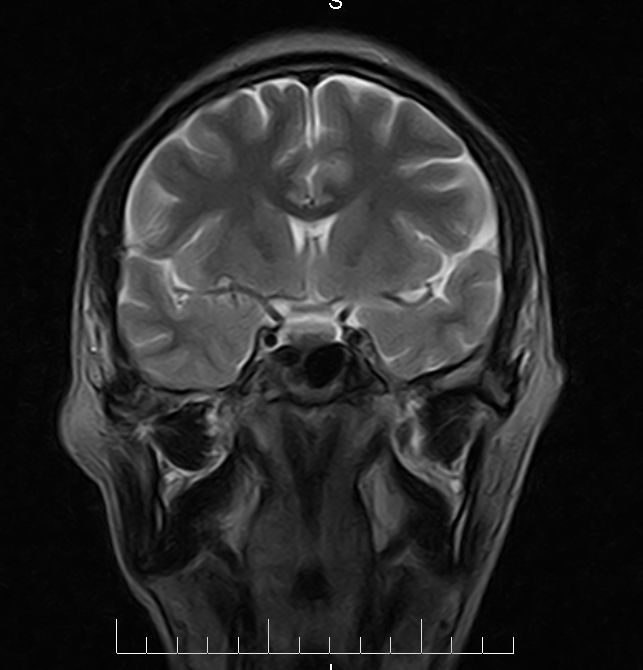

标题: MRI2379:30岁,男,癫痫10年,请各位看一下;CT示:左颞叶钙 [打印本页]

标题: MRI2379:30岁,男,癫痫10年,请各位看一下;CT示:左颞叶钙

左颞叶区见不规则点状混杂信号影

支持2楼 左颞叶区见不规则点状混杂信号影,考虑动静脉畸形。

考虑左侧颞叶脑血管畸形(avm)。----t1低等高混杂信号,t2等高信号周边较多流空血管影[冠状位明显],mra左侧大脑中动脉受压,远侧聚集.